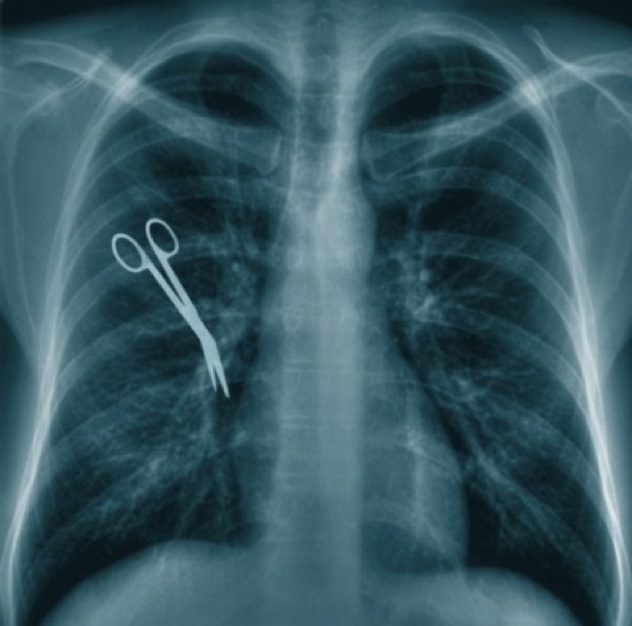

1. Pinset

Daryoush Mazarei merupakan korban malapraktek pasca sebuah operasi di University of Pittsburgh Medical Center (UPMC). Dia merasakan sakit yang luar biasa pada hari-hari setelah operasi tersebut.

Setelah berkali-kali komplain selama satu bulan, akhirnya Mazarei melakukan CT scan. Ternyata, ditemukan sebuah pinset yang tertinggal dalam rongga perut ketika operasi yang lalu.